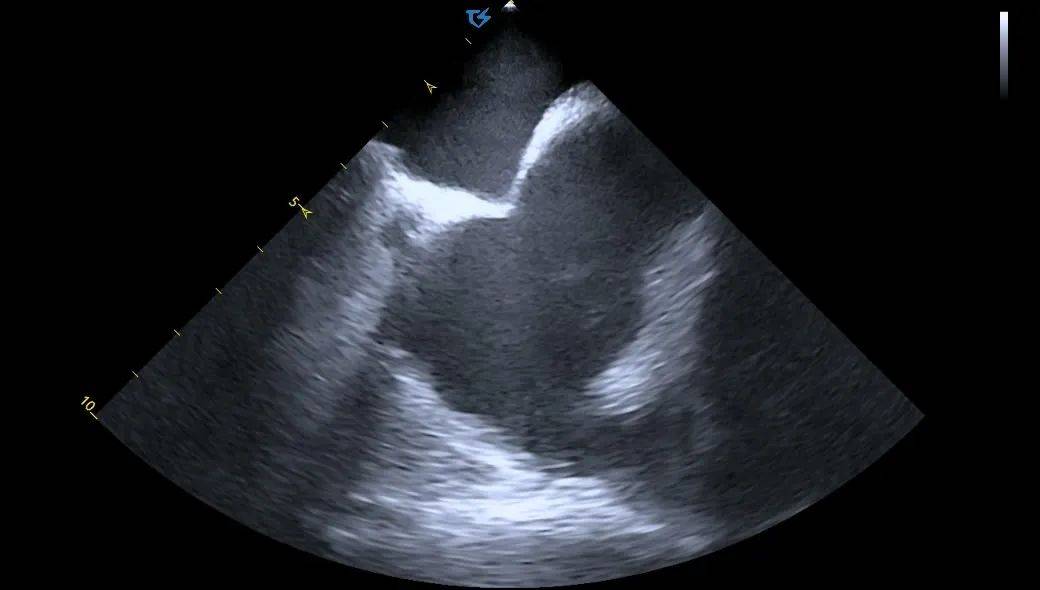

LSPV消融:

LSPV口内消融_ICE直视下脉冲导管以网篮形态与肺静脉贴靠

LSPV前庭消融_ICE直视下,显示脉冲导管以花瓣形态与肺静脉贴靠

ICE直视下,CP导管呈现网篮形/花瓣状贴靠在左上肺静脉,并可观察到导管进入肺静脉的深度&贴靠情况